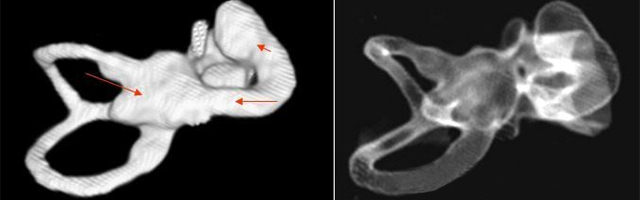

主要依靠顳骨高分辨CT和內(nèi)耳MRI。

雙側(cè)內(nèi)耳畸形:左側(cè)無內(nèi)耳迷路及內(nèi)耳道機(jī)構(gòu),為米歇爾畸形;右側(cè)空耳蝸及前庭擴(kuò)大,為先天性耳蝸畸形